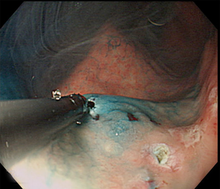

早期胃がんでは、お腹を切らずに内視鏡により切除するESD(内視鏡的粘膜下層切開剥離術) で治せるようになりました。内視鏡的技術と機器は著しく進歩しており、特にITナイフ、フレックスナイフ、フックナイフなどの処置具の登場、高周波発生装置の進化は内視鏡治療成績を上げています。

ESDとは、病変の周囲の粘膜を切開した後に粘膜下層を剥離して病変を切除する確実な内視鏡治療です。

従来のEMR(内視鏡的粘膜切除)という方法では小さな病変しか切除できませんでしたが、ESDは2cmをこえる大きながんの場合でも病変を一括に切除できる確実な内視鏡治療であり、癌の取り残しが少なく、再発する危険性もとても少ないです。

(1)がん病変を確認した後に、病変部に色素撒布をして、十分な観察を行って、切除範囲をマーキングします。

(2)周囲に局注し、プレカット(ITナイフを入れる小さな孔を作成)をします。

(3)マーキングした部位の外周を全周切開します。粘膜下に局注液を注入して病変部を盛り上げ、その粘膜下層を剥離して一括切除します。

(4)最後に切除した粘膜を回収して、病理組織学的に検索します。